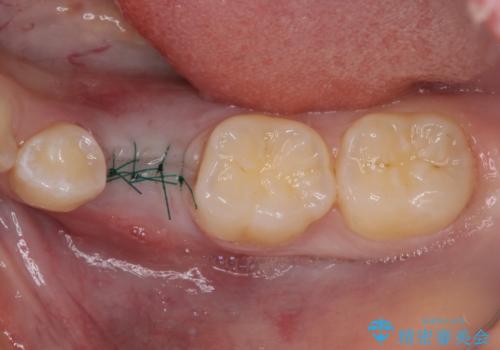

矯正治療が終わるタイミングに合わせてインプラントの埋入を行っていたので、矯正治療を終了すると同時にセラミック補綴治療を行えました。

短期間でしっかりと治療を終えることができました。